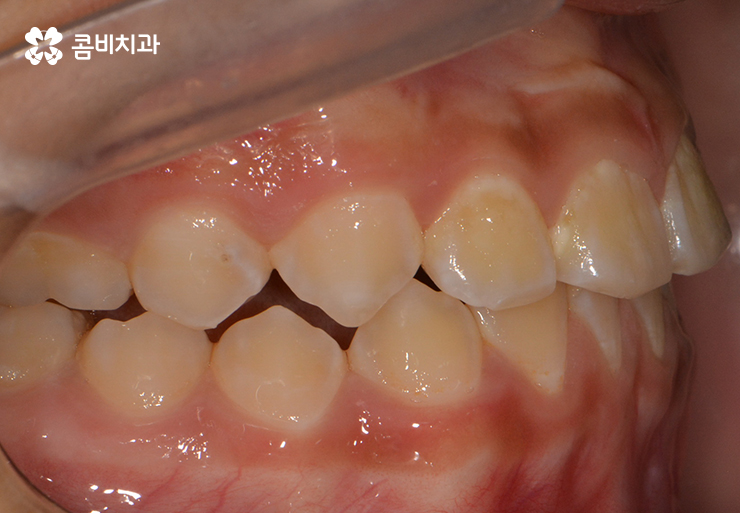

많지만 위 사례 이미지와 같이 교합이 맞물리지 않는 경우에는

심미적인 부분을 떠나서 식사를 할 때마다 불편함을 느끼게 된다거나

발음이 새고 턱관절에 무리가 올수 있는 등 건강 상의 문제가 발생할 수 있습니다.

(위턱과 아래턱의 성장 불균형으로 인해 주걱턱이 발생한 사례)

위와 같은 사례를 부정교합 중에서도 반대교합이라고 하는데

성장기에 턱이 성장을 할 때 아래턱이 과도하게 발달을 하거나

반대로 위턱의 성장이 부족한 경우에 이와 같은 주걱턱 증상이 발생할 수 있습니다.